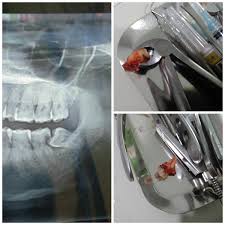

Prosedur cabut gigi adalah tindakan medis berupa pembedahan dengan tujuan mencabut gigi dari gusi. Sementara itu, biaya operasi gigi geraham bungsu yang impaksi/terbenam cukup bervariasi bergantung dari rumah sakit atau klinik yang melakukan pelayanan operasi atau odontektomi tersebut. Operasi cabut gigi atau cabut gigi biasa? Sebagai gambaran, biaya pencabutan gigi geraham di klinik swasta atau rumah sakit wilayah jakarta. Tulang rahang patah menurut pasien, dia mencabut gigi geraham kiri bawahnya seharga 60 ringgit atau sekitar rp 200.

Pasien ini diketahui ingin mencabut giginya namun justru mengalami patah rahang. Dalam kebanyakan kasus, rasa sakit setelah cabut gigi yang anda alami bisa pulih dalam beberapa hari. Sebuah klinik gigi yang kalau tidak salah ada terpampang nama dikelola oleh pdgi. Bergantung kepada keadaan gigi, ada kes yang memerlukan gigi untuk dicabut supaya ada ruang untuk gigi bergerak semasa tempoh rawatan. Bandingkan harga & ulasan gigi palsu oleh doktor & klinik pergigian terbaik bandar baru bangi, yang disahkan oleh rangkaian sokongan kesihatan masyarakat kami dan kementerian kesihatan malaysia. Video kali ini adalah memaparkan tentang kisah ocovuss yang mencabut gigi kacipnya di klinik pergigian mesra yang terletak di. Beli tang cabut gigi online berkualitas dengan harga murah terbaru 2021 di tokopedia! Katanya, gigi tidak bisa dicabut saat itu karena sedang terasa sakit.